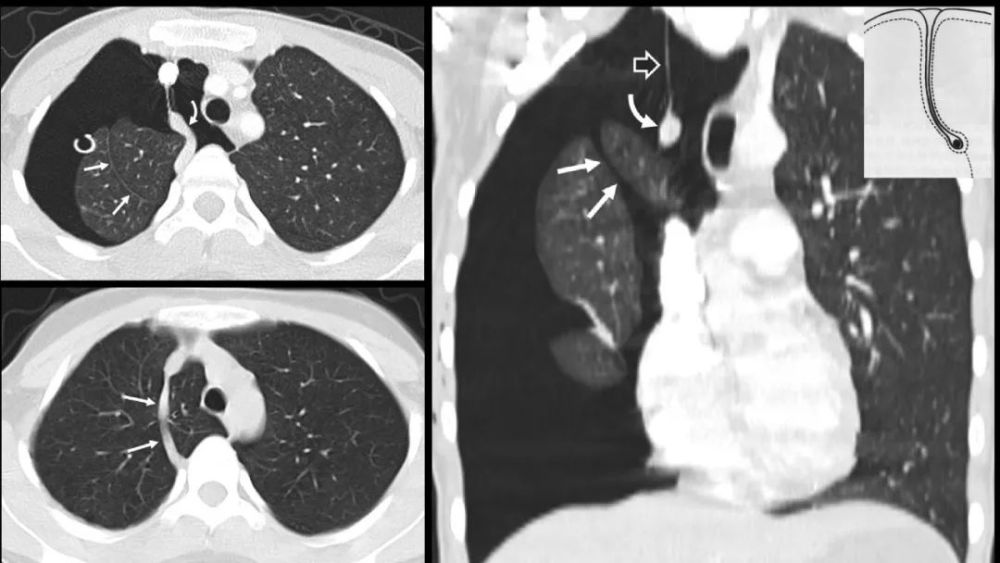

奇 裂

奇静脉分隔右肺上叶尖段

不是真正的附叶 , 因为没有自己的支气管 解剖标本的发生率为1% , M:F=2:1

X:细线状隆起(相对于纵膈) , 穿过右肺尖 , 前位上纵膈胸片可?气体

CT: 奇裂从SVC和气管后穿过